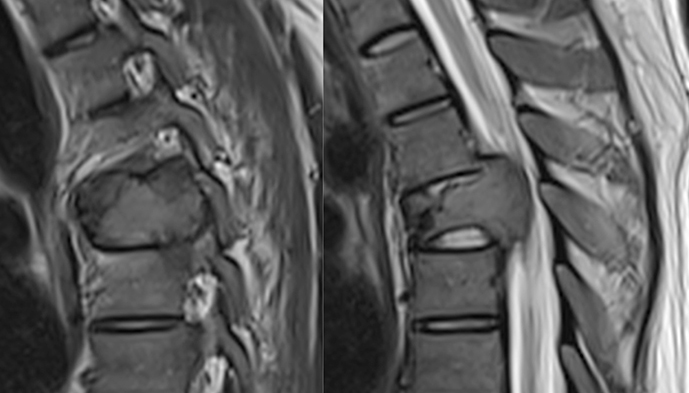

- H MRI έχει χαρακτηριστική απεικόνιση με ενδιάμεση ένταση σήματος του σώματος του σπόνδυλου, σε εικόνες T1 και μετρίως αυξημένη σε T2. H πλήρης έκταση του όγκου είναι εμφανής μετά την χορήγηση ενδοφλεβίως παραμαγνητικής ουσίας. Η παρουσία λίπους στο οστικό τμήμα του όγκου προκαλεί chemical shift artifact, ενώ η απουσία λιπώδους ιστού στο έξω-οστικό τμήμα του, είναι υπεύθυνη γιά το χαμηλό σήμα σε T1 εικόνες.